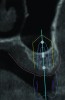

3D radiographic scans obtained using the single scan protocol can be combined with digital mock-ups performed on intraoral optical scans or scans of casts,20 using the existing natural teeth as fiduciary markers. Different masks for bone, teeth, gingiva, and implants can be designated and processed (Figure 13 and Figure 14). This technology allows for greater accuracy, since implant position will be determined based on natural teeth (fiduciary markers) that are likely to be more stable and accurate than fiduciary markers placed on a radiographic guide.

(13) An optical scan of patient’s teeth and diagnostic wax-up was combined with CBCT to facilitate treatment planning of implant placement. Note that there is a need for sinus augmentation to accommodate a dental implant on the right image (blue: tooth contours determined from wax-up/optical impression, red: soft tissue outline).

Figure 13

(14) An optical scan of patient’s teeth and diagnostic wax-up was combined with CBCT to facilitate treatment planning of implant placement. Note that there is a need for sinus augmentation to accommodate a dental implant on the right image (blue: tooth contours determined from wax-up/optical impression, red: soft tissue outline).

Figure 14